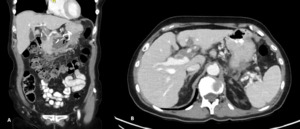

Further evaluation with Doppler ultrasound demonstrated non-occlusive bland thrombus within the common hepatic and left hepatic arteries. A subsequent CT angiogram (CTA), performed four weeks after the initial CT, confirmed the presence of multiple visceral pseudoaneurysms involving the hepatic arterial system. These included aneurysms of the right hepatic artery measuring 5.5 mm and 5.8 mm, intermediate hepatic artery aneurysms measuring 7.7 mm, 5.7 mm, and 14 mm, and a left hepatic artery aneurysm measuring 10.4 mm. Additionally, the coeliac trunk appeared diffusely aneurysmal with associated luminal irregularity (figure 3). All aneurysms demonstrated interval enlargement compared with prior imaging (Figure 2). Notably, during this period, the patient’s inflammatory markers and liver function tests had normalised.

Two weeks later, a repeat CTA demonstrated interval resolution of the previously identified pseudoaneurysms arising from the right, intermediate, and left hepatic arteries. The right and intermediate hepatic arteries were of markedly reduced calibre and tapered shortly after their origins, suggesting proximal arterial occlusion. The absence of contrast opacification within the previously visualised aneurysms was attributed to occlusion of the feeding vessels. Peripancreatic inflammatory stranding had mildly improved, and the previously noted lesser sac collection was no longer visualised (Figure 4).